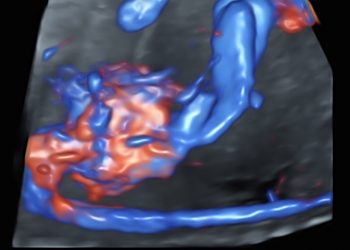

Cari soci, questo mese un nuovo video "How to do", dedicato all'utilizzo del 3D nello studio del volto fetale. Grazie...